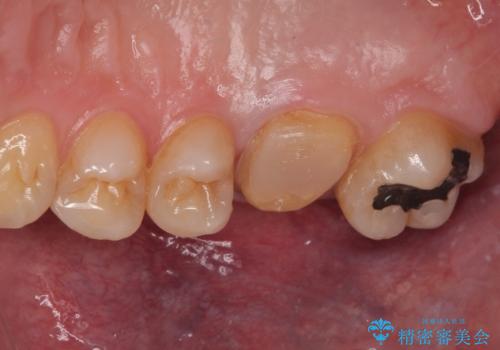

拡大鏡視野下で詰め物と虫歯の除去を行い、詰め物の範囲が大きかったためオールセラミッククラウンに適した形に整えました。

型どりはシリコーン印象材にて精密印象をしています。

痛みもなく、適合もよく、機能的に問題もなく、見た目も満足されていました。

嚙む力(咬合力)がとても強い方なのでナイトガードを今後使っていただく予定です。